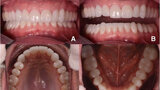

Fig. 14. Fotografías intraorales del tratamiento finalizado. a y b Vista frontal. c Vista oclusal de la mandíbula superior. d Vista oclusal de la mandíbula inferior.